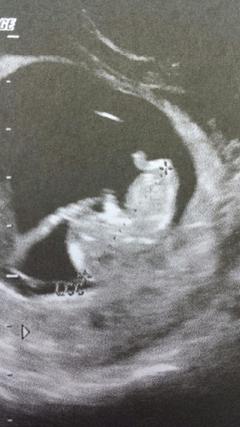

Ce fut un choc lorsque le test est devenu positif… J’attendais mes règles pour pouvoir me poser un implant sous cutanée. Mais elles ne sont jamais arrivées ! La cause : j’étais enceinte et lorsque je m’en suis aperçu, j’étais à peu près à deux mois et demi presque trois !